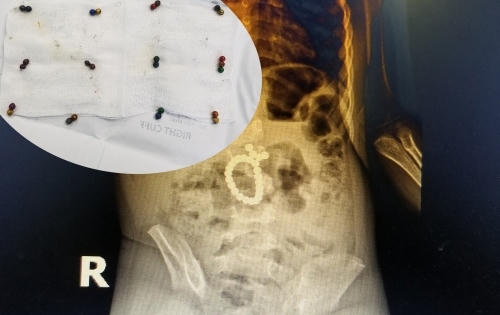

Sau 3 giờ phẫu thuật, các bác sĩ đã gắp 25 viên bi ra khỏi bụng bé T., đồng thời tiến hành khâu kín vị trí ruột thủng thành công.

Một cháu bé sau nhập viện trong tình trạng đau bụng, đã được các bác sĩ kiểm tra, phát hiện ra hơn 10 hạt nam châm với nhiều hình dạng trong ruột.

Bệnh viện Nhi Đồng 2 phẫu thuật cấp cứu bé trai 4 tuổi thủng ruột do nuốt 8 thanh nam châm.